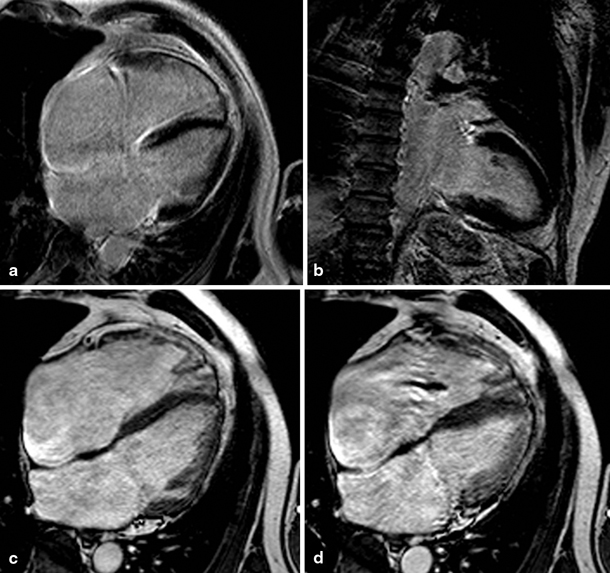

A total of 21 patients with IHD had infarcts in the LAD territory and 2 patients in the LAD and LCX territory (Fig. 1). Infarction of the RV free wall was recognised in only one patient of the IHD group: a small area of late enhancement of the RV apex was visible on CMR images. This patient had a transmural infarction in the LAD territory showing late enhancement from the anterior wall to the apex of the LV continuing to the RV apex (Fig. 2). None of the patients with DCM had focal fibrosis of the RV free wall myocardium on CMR late enhancement images.

Fig. 1

Late gadolinium enhancement (a, b) and cine (four-chamber view in end-diastole (c) and end-systole (d)) magnetic resonance images of a patient with a large myocardial infarction (left ventricular ejection fraction 15 %) of the left anterior descending coronary artery (right ventricular ejection fraction 56 %)